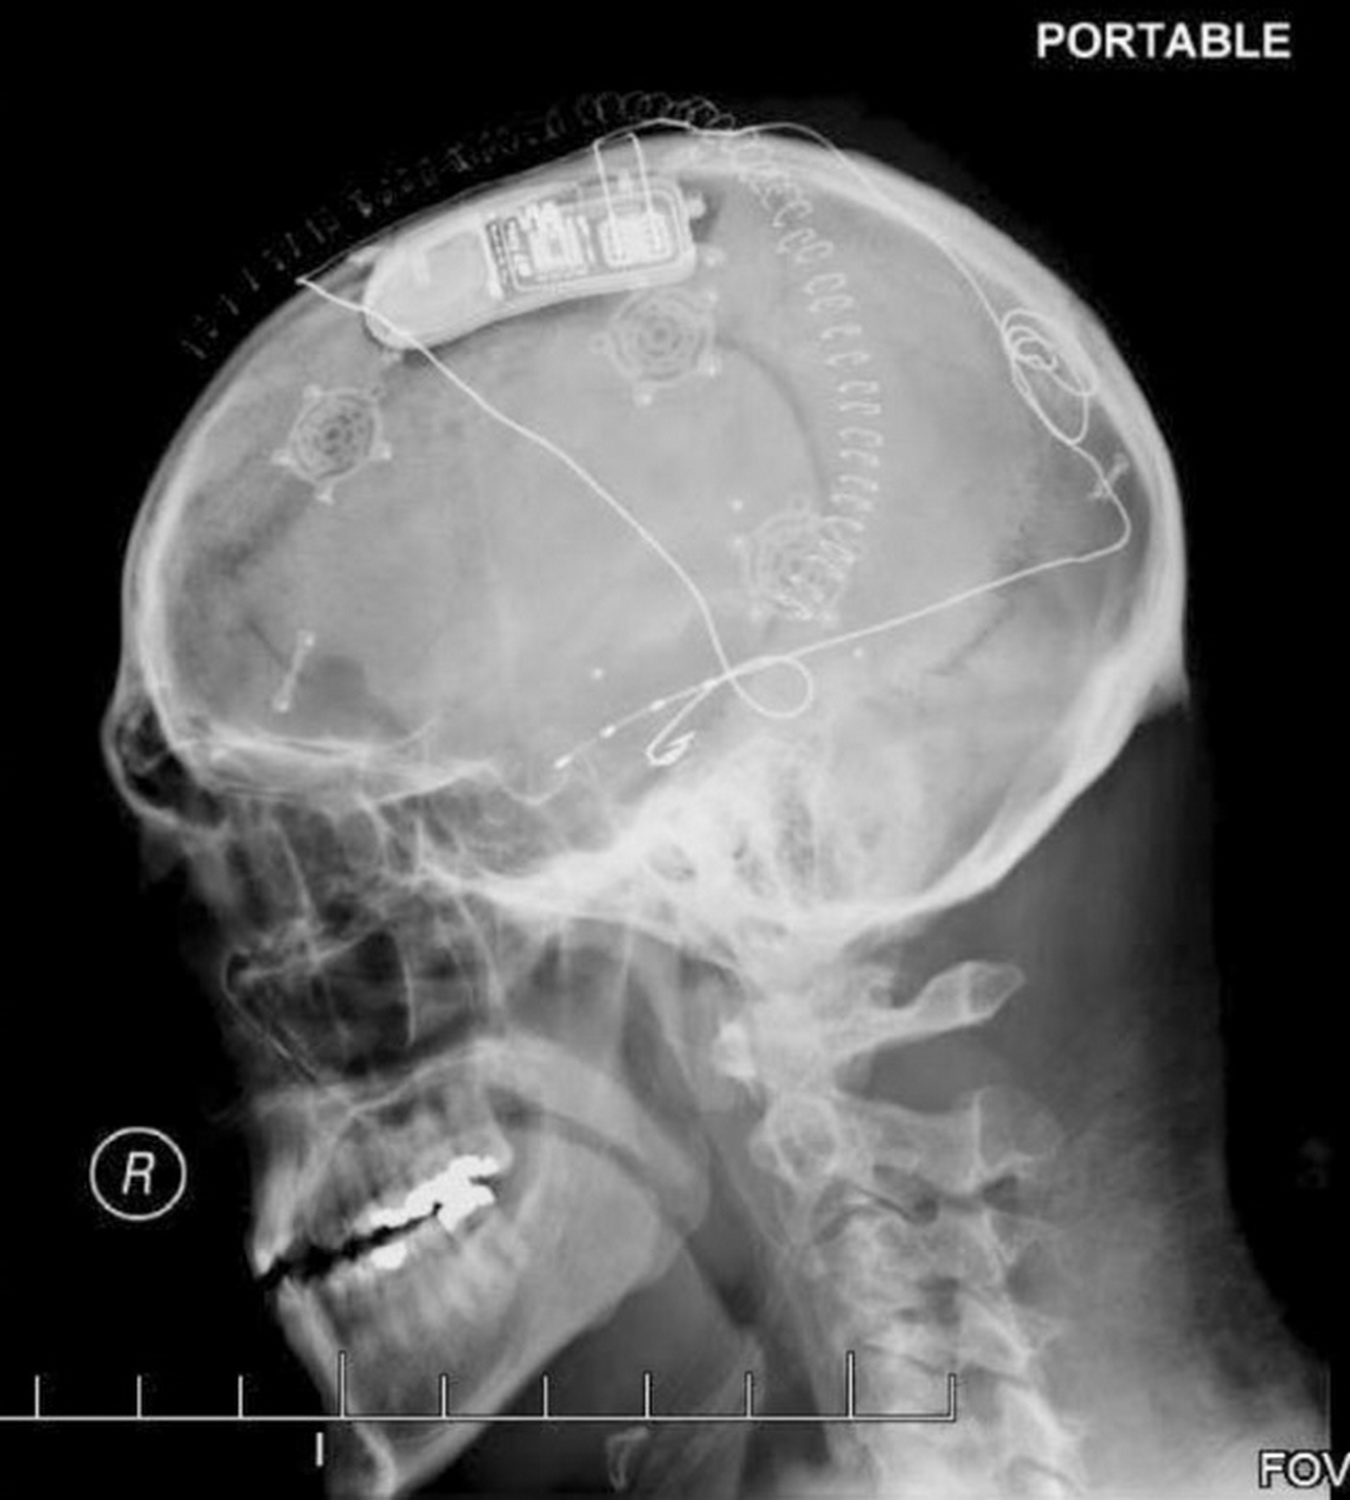

Устройства RNS, подобные этому, предотвращают эпилептические припадки. Провода идут к участку мозга, где начинается припадок, а скобы удерживают кости черепа после трепанации. Система RNS, разработанная в Кремниевой Долине, состоит из крошечных имплантированных нейростимуляторов